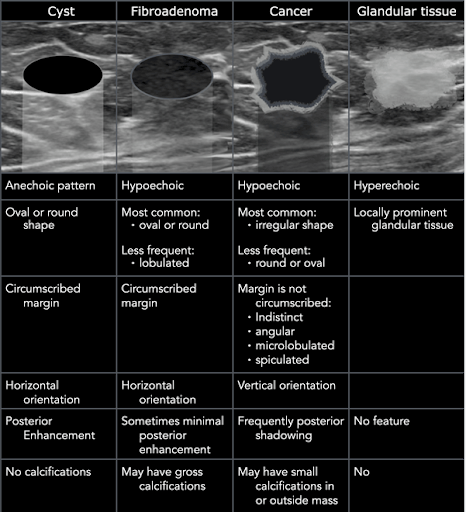

When performing breast ultrasound, describe the lesion using the following features (Malherbe 2024):

-

Shape: Oval, round or irregular

-

Position: Describe relative to a clock face

-

Orientation: Parallel or not parallel

-

Margin: Circumscribed or not, further characterized as indistinct, angular, microlobulated, or spiculated

-

Echo pattern: Anechoic, hyperechoic, complex cystic and solid, hypoechoic, isoechoic, heterogenous

Posterior features: No posterior features, posterior acoustic enhancement, posterior acoustic shadowing, or combined pattern

From “The Radiology Assistant: Ultrasound of the Breast”

Most common benign morphologic features (Flory 2020):

-

Smooth and well-circumscribed margins

-

Hyperechoic, isoechoic, or mildly hypoechoic in echogenicity

-

Thin echogenic capsule or well-defined capsule border

-

Ellipsoid shape, wider than tall appearance

-

Macrolobulated; <3 lobulated margins

-

Posterior acoustic enhancement

Most common malignant morphologic features (Flory 2020, Vincent 2020):

-

Hypoechoic mass, on occasionally hyperechoic in appearance

-

Spiculated margins

-

Ill-defined borders, architectural distortion of surrounding soft tissue

-

Posterior acoustic shadowing

-

Taller than wide appearance

-

Presence of microcalcifications